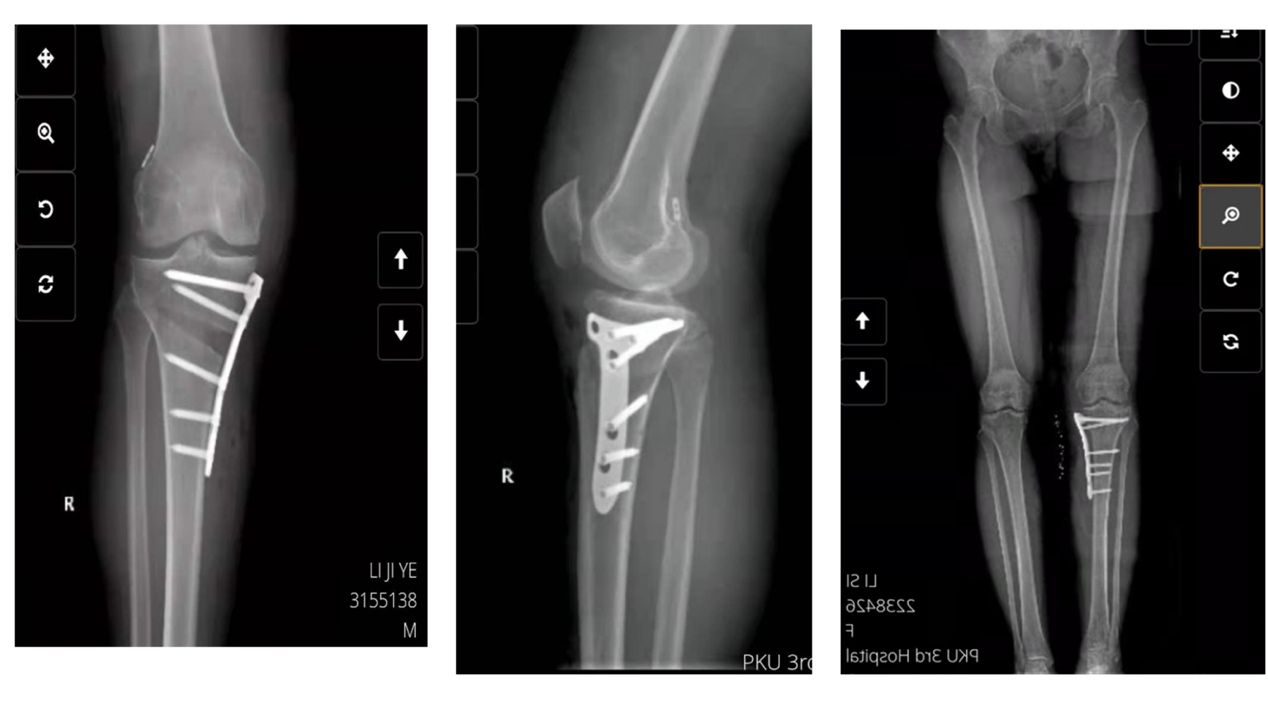

近年来我们还开展了个性化膝关节截骨手术,适用于年纪较轻的单间室骨关节炎患者。膝关节截骨术以胫骨截骨为主,涵盖股骨及双截骨,闭合及撑开均涉及。并对合并关节不稳的患者进行膝关节韧带重建。

胫骨高位截骨术后x线片